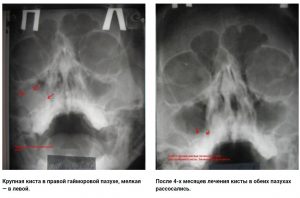

Первый зафиксированный случай рассасывания кист и полипов носа, в истории медицины, принадлежит нашей клиники!

Впервые в истории медицины киста и полипы рассосались в Москве в нашей клинике.